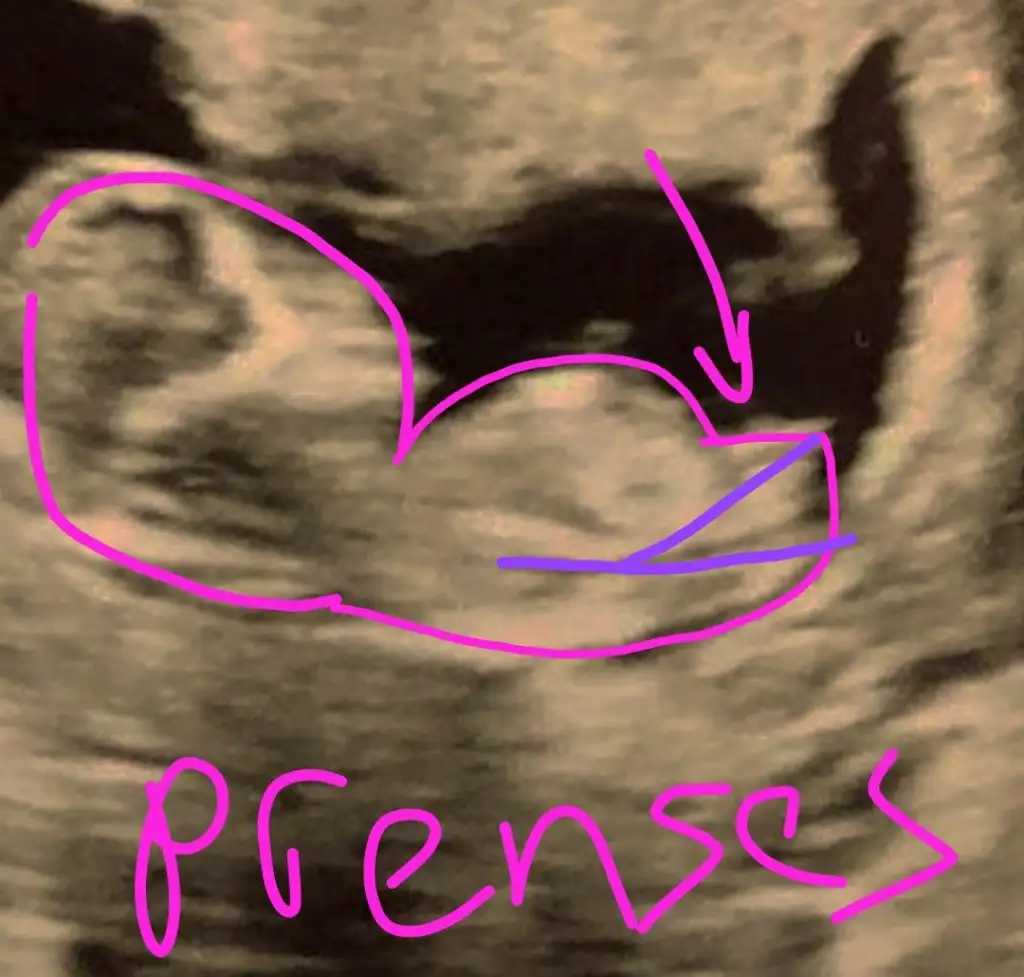

Popoya paralel değilCanım bana parelel gibi görünmüştü kaç gündür anlamaya çalışıyorumresim üzerinde tarif edebilir misin nasıl dik göründü sana

![]()

Aa Bende onu kordon sanıp şunu nub sandım

Değil.orasi popo uç tarafiAa Bende onu kordon sanıp şunu nub sandım![]()

dik olan göbek kordonu sanırım bnce nub paralelBen de çok kız hissediyorum ama doktorumuz erkek dedi ,bir de sizin tahminlerinizi almak istedim :) siz benzettiniz mi?

Ben de öyle görüyorum sanki ,ve hislerim aşırı derecede kız yönünde..ama doktor pipi çıkıntısı gördüğünü söyledi sizlerden duymak istedim birdedik olan göbek kordonu sanırım bnce nub paralel

Kordon orda olmazdik olan göbek kordonu sanırım bnce nub paralel